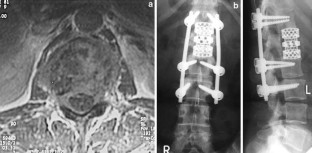

Introduction: The objectives of surgical interventions for tumoral lesions of the spine include the establishment and improvement of tumor-related symptoms. Anterior tumor resection followed by reconstruction indicated if surgical treatment allowed a marginal removal of the tumor or could extend the individual survival rate in combination with adjuvant therapy options. Sufficient re-stabilization depends on adequate anterior column reconstruction. The purpose of this retrospective study was to present our experiences and results after anterior tumor resection followed by reconstruction with the expandable vertebral body replacement device (VBR, Ulrich, Germany) based on clinical application over 4°years. Patients and methods: We carried out an anterior tumor resection followed by reconstruction using an anterior extendable device in 32 patients with different spine tumors between 1996 and 2000. A retrospective evaluation was executed considering the patients medical records and radiological findings. Additionally, a clinical and radiological investigation of still living postoperative patients was carried out. Results: The mean surgical time of all evaluated patients was 317.2 min. The average blood loss was 1,272.5 ml. According to the Tokuhashi score, patients with a postoperative survival time of at least 12 months demonstrated a score value ≥9 points. According to our evaluated patients group metastatic lesions of the spine represented the largest group (78.1%). The average survival rate of this group amounted to 18.4 months postoperatively. Considering primary tumors the average survival rate at the time of last re-examination amounted to 34.8 months postoperatively. Preoperative neurological pathologies were present in 12 patients (Frankel stage C--D). During the postoperative monitoring period 58.3% of the patients demonstrated an improvement in initial neurological findings. There were no intraoperative complications or perioperative deaths. Implant dislocations were not observed. Conclusion: On account of the underlying, the anterior tumor resection with supplementary instrumentation represented a sufficient procedure in spinal tumor surgery. Adjuvant therapy can influence the postoperative survival period positively in addition to the surgical procedure. Following anterior tumor resection, extendable vertebral body replacements like the VBR device provide immediate spine stability by excellent defect adaptation. With regard to their intraoperative flexibility, expandable cages are more advantageous in contrast to non-expandable implants or bone grafts.